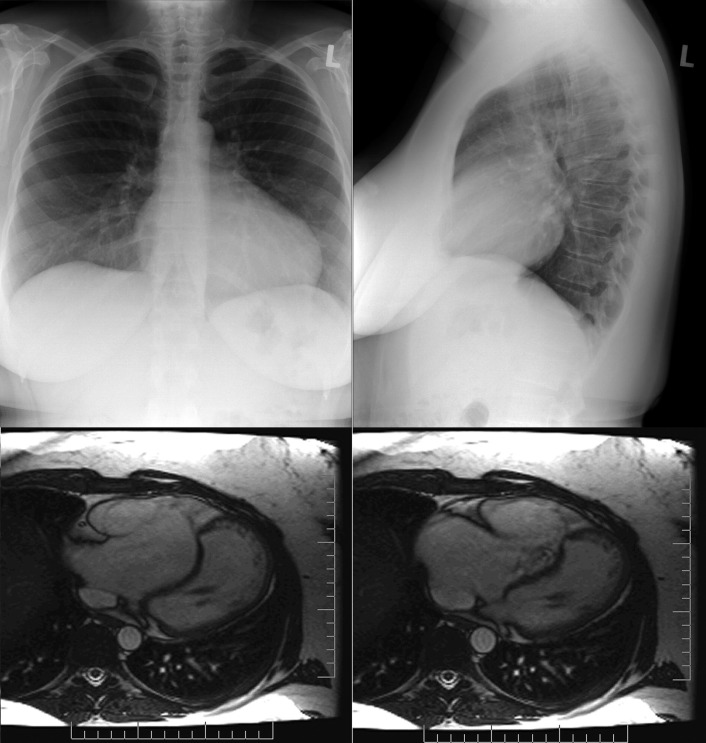

Chest radiographs and cardiac magnetic resonance (CMR; steady-state free precession [SSFP]) images of a patient with Ebstein’s anomaly. Note the signs of right heart chamber enlargement, the raised apex, and the small pulmonary artery. The CMR images reveal the atrialization of the right ventricle, marked enlargement of the right atrium and atrialized ventricle, and tricuspid regurgitation.